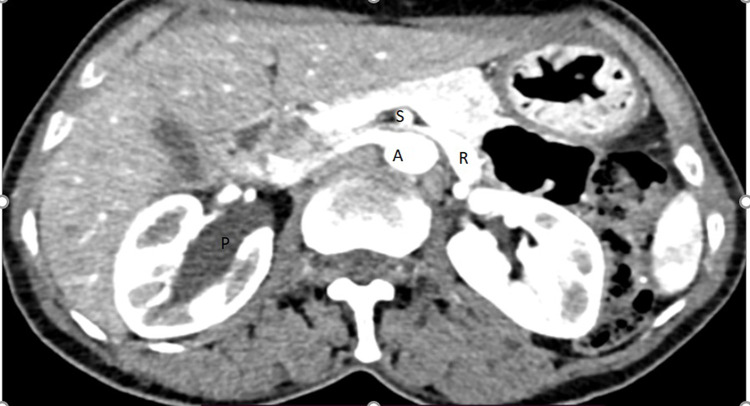

我们报告了一例罕见的左侧胡桃钳综合征和右侧输尿管盆腔交界处梗阻(UPJO)并发症,该患者为成年女性,在出现间歇性双侧侧腹疼痛后经 CT 尿路造影确诊。为此,我们为她实施了安德森-海因斯肾盂成形术(Anderson-Hynes pyeloplasty)以治疗右输尿管盆腔梗阻,最初是在腹腔镜下进行的,但由于支架植入困难而改为开腹手术。她术后恢复顺利,术后第三天就出院了。胡桃钳综合征的症状对患者来说并不严重,因此我们计划对她进行保守治疗。

We report rare case of concomitant left nutcracker syndrome and right ureteropelvic junction obstruction (UPJO) on adult female patient diagnosed by CT urogram after she presented with intermittent bilateral flank pain. For this we did Anderson-Hynes pyeloplasty for right ureteropelvic obstruction, it was laparoscopic initially but due to difficulty of stenting it is changed to open. She had smooth post-op course then discharged on 3rd post-op day. Symptoms of nutcracker syndrome are not that much bothersome for the patient so we planned to follow her conservatively.